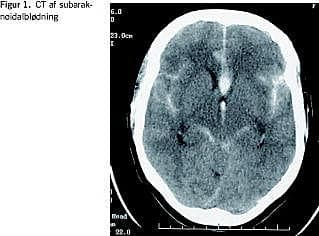

Ved klinisk mistanke om SAH udføres der computertomografi (CT) af kraniet. Skanningen viser typisk blod i de basale cisterner, evt. bredende sig ud i fissura sylvii på en eller begge side(r). Ofte ses der gennembrud af blod til ventrikelsystemet og hæmatomer i subaraknoidalrummet eller hjerneparenkymet (Figur 1 ). CT'en vil ud over at stille diagnosen i en del tilfælde også kunne give et fingerpeg om aneurismets placering. En mere sikker viden om lokaliseringen kan opnås ved CT-angiografi. Magnetisk resonans-skanning vil sjældent være indiceret ved akut SAH, idet mindre blødninger kan overses, og patienterne kan have svært ved at medvirke i undersøgelsen. I de tilfælde, hvor man ikke finder blødning ved CT, bør der suppleres med lumbalpunktur for sikkert at be- eller afkræfte SAH.